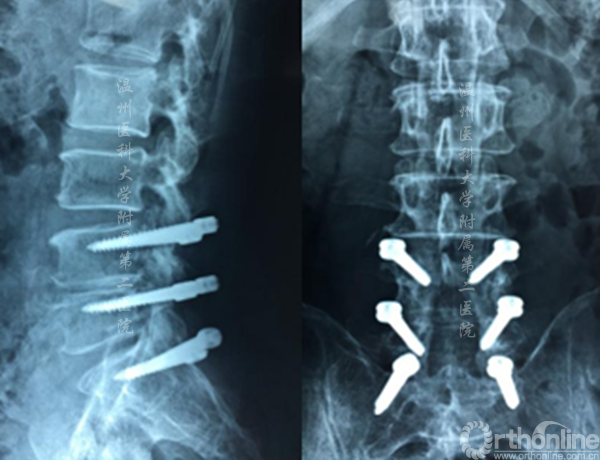

术后X线显示CBT螺钉未松脱、断裂,螺钉位置良好

案例3

4-1Dynesys术后3年,腰3.4椎管狭窄。

术前X线资料

术中显露置钉的过程

术中透视资料

术后X线资料(左侧)及术后切口对比(右侧)